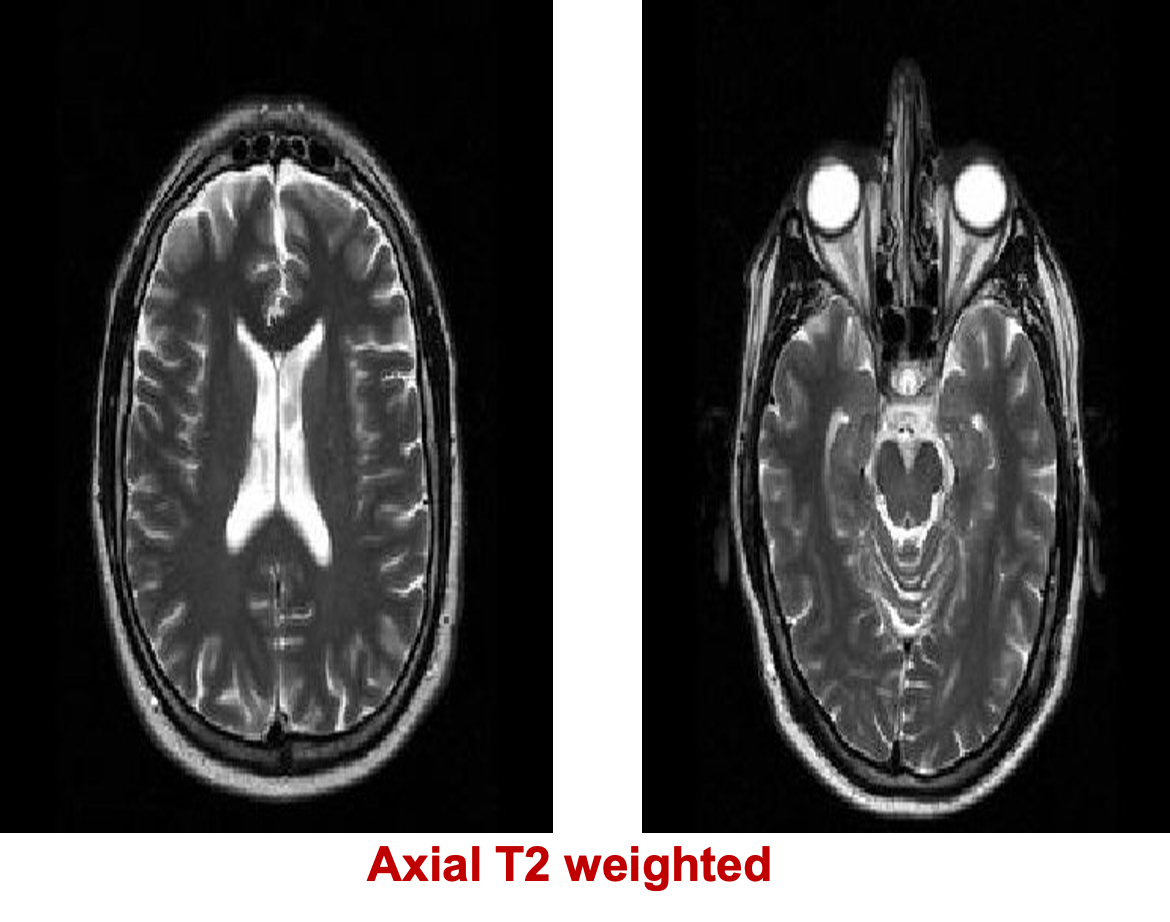

T1 WIs [CSF BLACK ] T2 WIs [CSF BRIGHT ]

T1 low signal / T2 high signal

- Fluids ( CSF, urine, pleural effusion, ascites.,…)

- Edema and infarctions

- Most of tumors